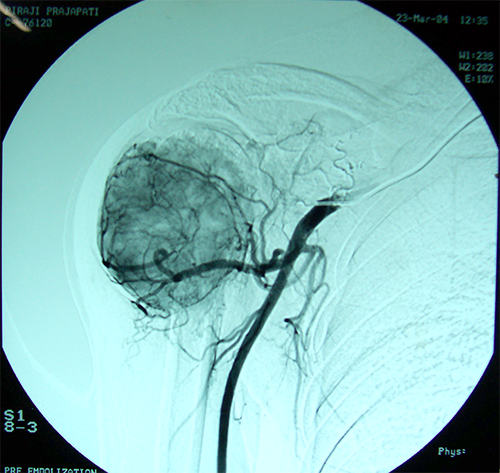

Case:6 Transfer of Scapula to Humerus

Angio-2

Angiogram